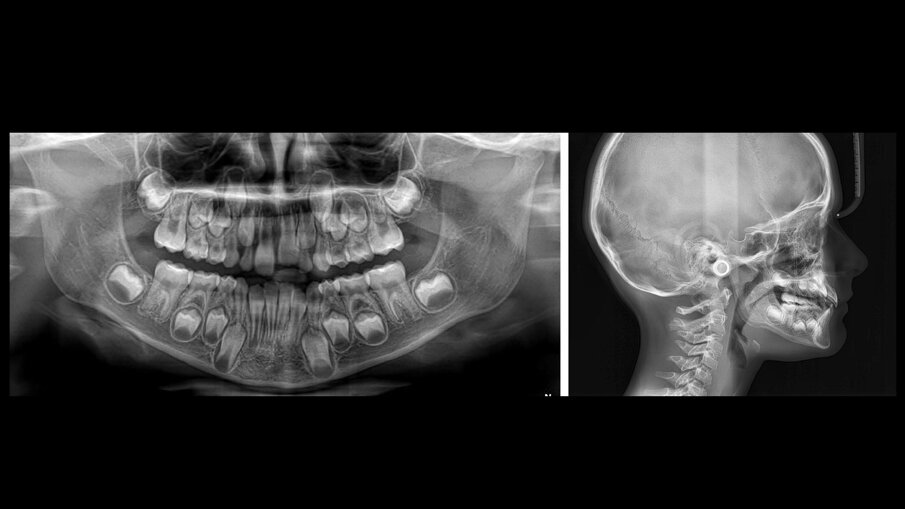

È possibile dunque affermare che il trattamento ortodontico eseguito con la sistematica Nuvola Genius ha raggiunto gli obiettivi prefissati di sviluppo d’arcata. L’ortopantomografia mostra uno stadio F secondo la classificazione di Demijrian, la risoluzione dell’affollamento della zona apicale intermedia e anteriore, mentre la teleradiografia laterale conferma la malocclusione di prima classe scheletrica mesodivergente (Fig. 8a-8b).

Figg. 8a, 8b_Record radiografici postrattamento.